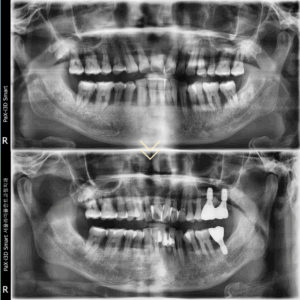

이번에 소개하는 환자분은 이러한

동탄역치과 치주치료의 효과를 잘 보여주는 사례입니다.

초진 내원 당시 환자분의 구강 내에는

28개의 모든 치아에서 치조골 파괴가

심하게 진행되어 있었고

치은연하치석이 거의 전 영역에

걸쳐 침착된 상태였습니다.

x-ray상에서 잇몸아래쪽 치아 옆에 뾰족하게

붙어있는 것들이 치은연하치석입니다.

이후 환자분은 6년 동안 매우 성실하게

치주치료와 유지관리를 이어가셨고

그 결과 대부분의 치아에서 치조골 재생이

관찰될 만큼 건강한 상태로 회복되었습니다.

최종 보철 완성 후 촬영한 사진에서는

임플란트를 식립한 부위의 치조골이

안정적으로 재생된 모습을 확인할 수 있었고